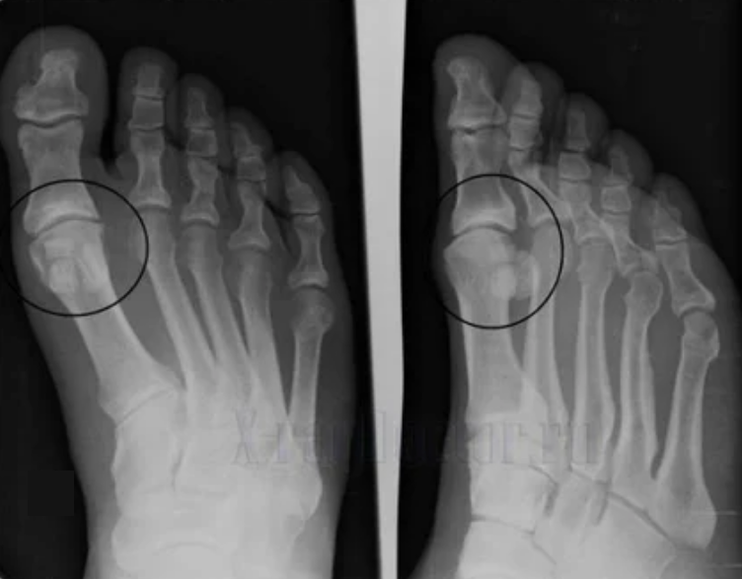

Per fare una diagnosi, i reumatologi studiano le lamentele del paziente e prescrivono un esame di raggi X. Molto spesso, la radiografia viene utilizzata in 2 proiezioni. Il medico esamina la presenza di disturbi distrofici nella cartilagine ialina e nelle articolazioni ossee. Se il divario articolare è ridotto, le ossa vengono deformate o appiattite, ci sono formazioni cistiche sulla superficie della cartilagine, gli osteofiti sono evidenti segni di artrosi. Durante l'ispezione, l'artrosi indica l'instabilità dell'articolazione: l'asse degli arti e la sublussazione è disturbato.

Spesso un'immagine a raggi X non è in grado di fornire informazioni complete sulla condizione del giunto. Per uno studio più approfondito, è prescritta la tomografia computerizzata, è efficace per esaminare le ossa. La risonanza magnetica è più spesso usata per studiare i tessuti molli.